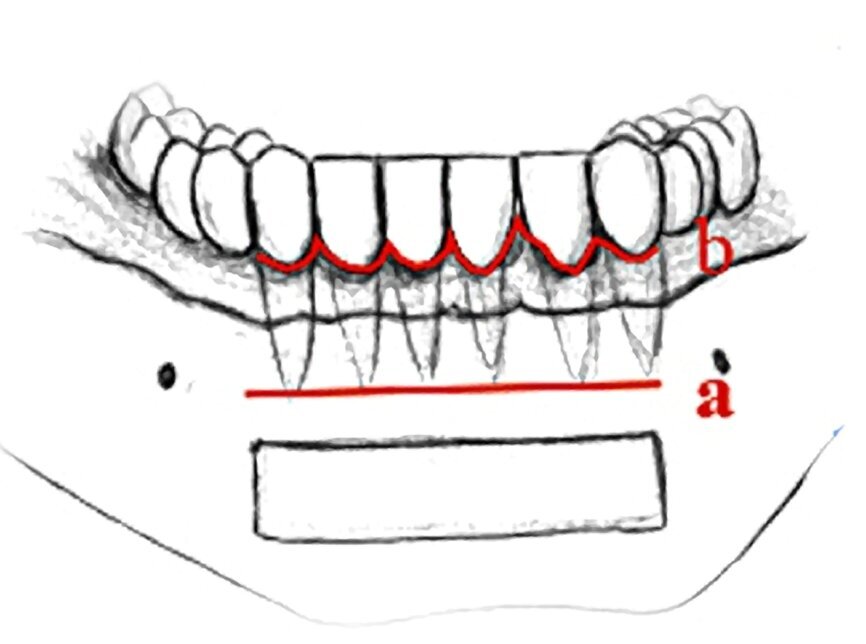

Fig. 1

Figura 1

2 INJERTOS EN BLOQUE

Los injertos onlay se emplean para el aumento de altura y/o anchura del reborde alveolar (< 3.5 mm de anchura) a través de la inserción de fragmentos o bloques óseos asociados o no a membranas con refuerzo de titanio en la zona receptora14,15. Esta técnica se lleva a cabo con la colocación diferida de implantes tras un periodo de curación de 6-9 meses16,17,18,19.

En la elección del tipo de material de injerto, se debe tener en consideración que ante hueso tipo I o II según la clasificación de Lekholm y Zard (frecuente a nivel mandibular), será preferible la aplicación de hueso autólogo por sus propiedades osteoinductivas, ostoconductivas y osteogénicas. No obstante, en hueso tipo III o IV según la clasificación de Lekholm y Zard (habitual en el maxilar superior), el tipo de biomaterial no será tan determinante20.